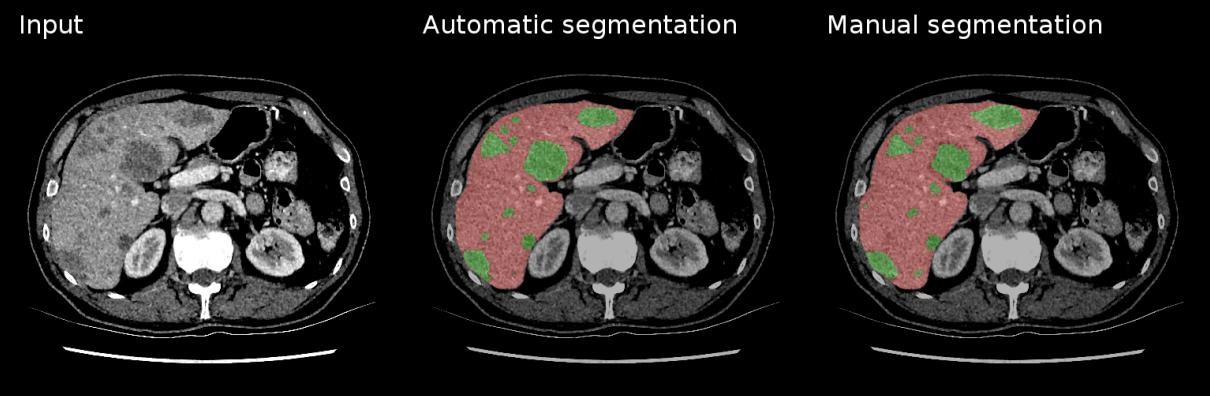

6. Image Segmentation¶

Task: Classify every pixel in an image - the most detailed form of visual understanding

Medical Applications:

- Organ segmentation for surgical planning and volume measurement

- Semantic Segmentation: Labels all pixels of the same class identically

- Instance Segmentation: Distinguishes between different instances of the same class

U-Net Architecture:

- Designed specifically for biomedical image segmentation

- Excellent performance with limited training data

- Key features:

- Encoder-decoder structure (U-shaped)

- Skip connections between corresponding encoder-decoder levels

tl;dr - For medical image segmentation, U-Net uses a U-shaped CNN. The encoder (left) extracts features at increasing granularities using convolutions and pooling. The decoder (right) then upsamples these features to recover the original image size with fine detail. Skip connections link encoder features to the decoder, combining "what" and "where" for precise segmentation.